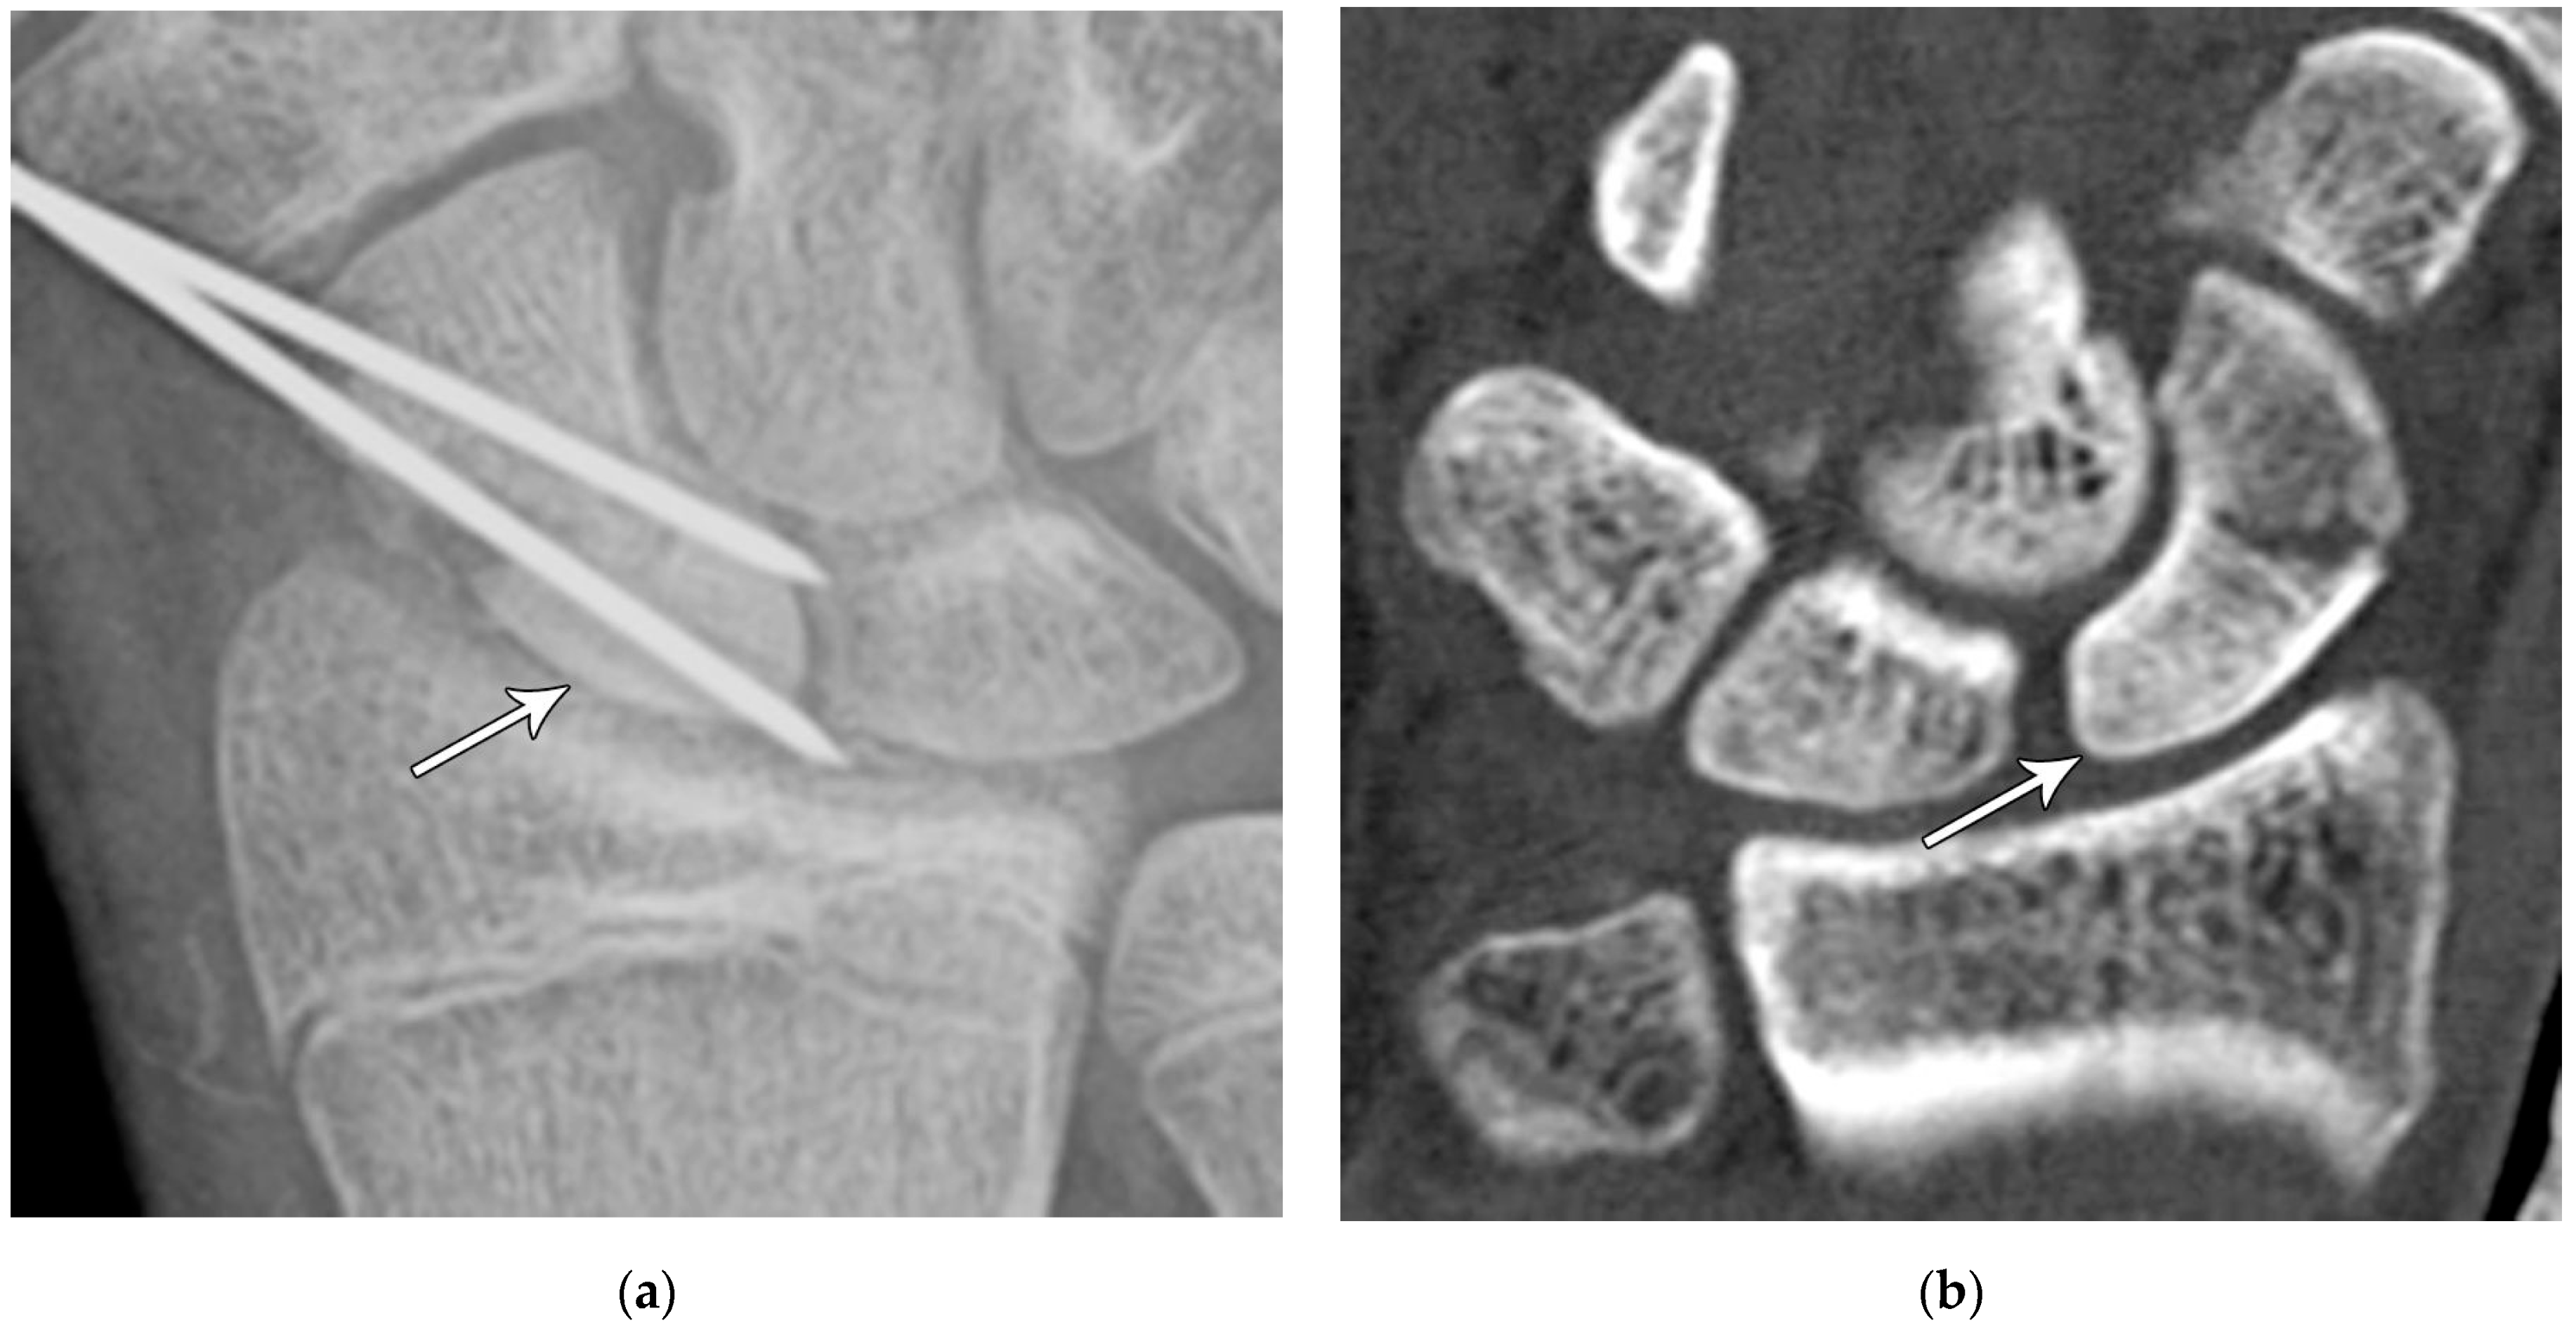

Figure 4. (a) Lateral radiograph of the wrist showing Humpback deformity (arrow) after a scaphoid fracture. (b) Sagittal CT reformation of the wrist showing the full extent of a humpback deformity with dorsal prominence at the site of the scaphoid fracture (arrowheads); image courtesy of Frank Gaillard, Radiopaedia.org, rID: 18269.

The majority of scaphoid fractures (70%) occur through the waist of the scaphoid, with 10% of scaphoid fractures involving the distal third, and 20% involving the proximal third (Figure 2 and Figure 3) [2,14]. With a scaphoid waist fracture, dorsal prominence at the fracture site due to dorsal angulation is known as humpback deformity (Figure 4). This deformity is important to recognize, as it needs to be more aggressively managed due to high risk of nonunion [15]. Additionally, if the two fragments unite with a humpback deformity, it may further destabilize the wrist. This humpback deformity may also be associated with dorsal intercalated segment instability (DISI), which will be covered in more detail later.